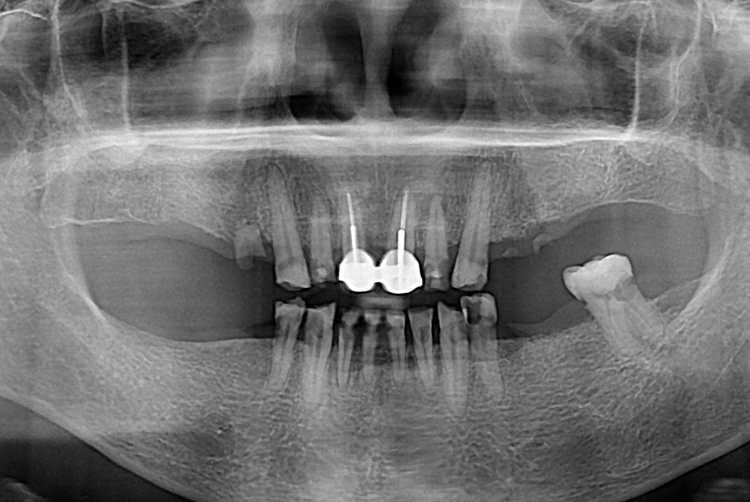

02f51832a1263f0919fc49bd2129faad.jpg

치료전 : 2019-10-08

세종치과는 많은 환자와 다양한 케이스를 바탕으로 항상 편안한 임플란트 수술을 제공하고자 노력하고,

오래동안 튼튼히 쓸 수 있는 임플란트 수술을 가장 큰 목표로 삼고 있습니다